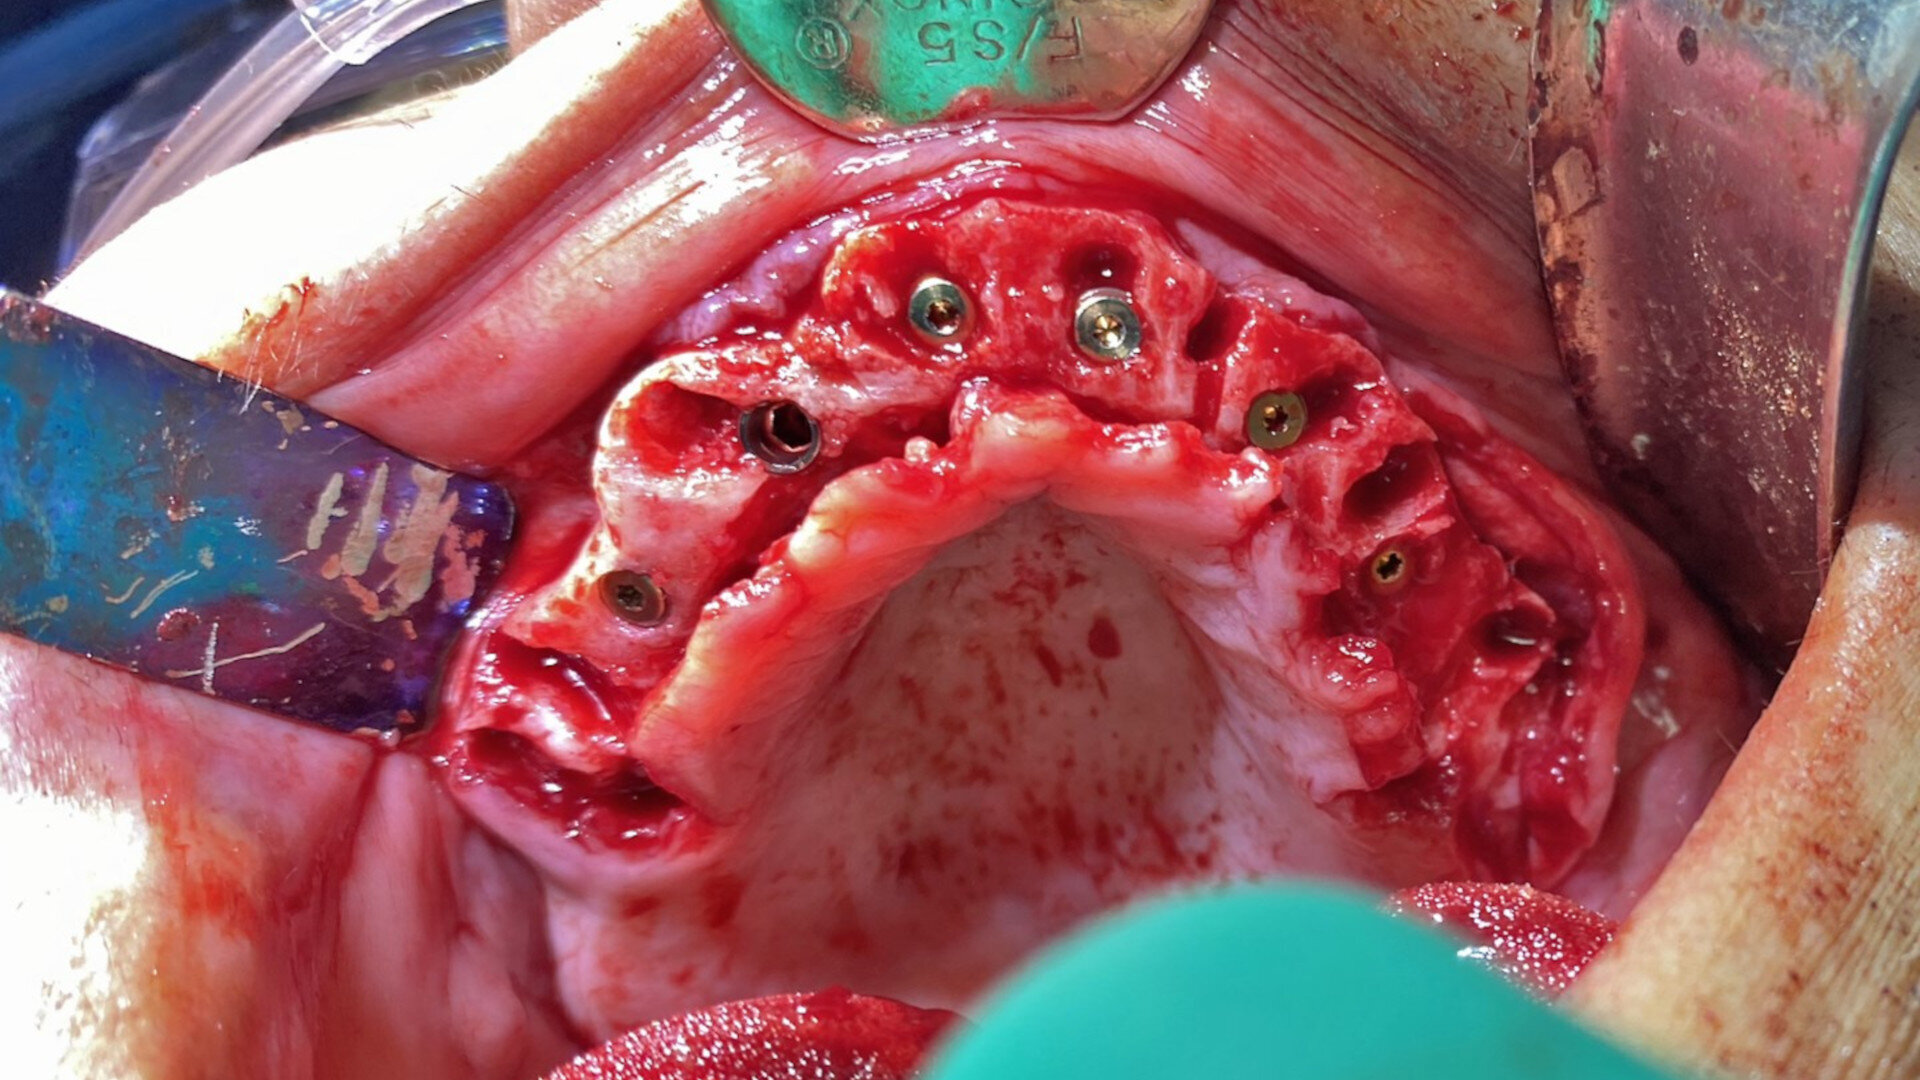

A full-thickness mucoperiosteal flap was elevated from the approximate areas of tooth #46 to tooth #35 and carefully reflected to expose the alveolar ridge. A bone reduction guide was placed over the site and fixated with four anchor pins. The bone was then reduced to the planned vertical height with rongeurs and flattened with carbide burs in a straight handpiece (Alveoplasty Kit, Meisinger USA). Based upon the 3D planning, the 3D-printed osteotomy drilling guide was designed to fit over the reduced bone and fixated in the same holes as the bone reduction guide (Fig. 13). The fixation pins were of two different lengths and secured the resin guide to the mandible (Fixation Kit, ROE Dental Laboratory). The osteotomies were prepared with sequential guided drills for accuracy, and five implants (Helix Grand Morse, Neodent) were placed approximately 2 mm subcrestally (Fig. 14). Although the implants all exhibited moderate insertion torque, the intermedullary bone density within the mandibular implant receptor sites was poor, as previously noted during the diagnostic phase.

Fig. 13: Surgical guide fixated to the mandible.

Fig. 14: Five implants placed as planned.